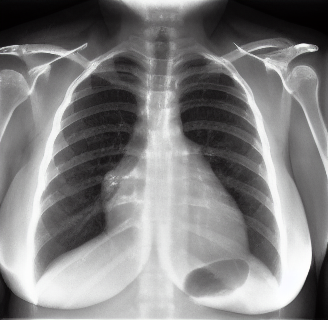

To fine-tune and evaluate our method, we utilize three medical imaging datasets. For the experiments on brain MR imaging, we utilize the ADNI-1 [52] and OASIS-3 [27] datasets which include longitudinal MR scans of Mild Cognitive Impairment (MCI), Alzheimer’s Disease (AD) or Cognitively Normal (CN) patients. For the chest x-ray experiments, we used the CheXpert [19] dataset, which is a large dataset containing over 224K chest radiographs of four categories: no finding (healthy), Cardiomegaly, Pleural Effusion, and Pneumonia. The datasets were preprocessed, and the final datasets consisted of scans (414 AD, 634 MCI, 2214 CN) for the brain dataset and 800 uniformly random samples from the chest x-ray dataset. The details of data preprocessing are reported in the supplementary material. All models for brain MR generation are evaluated on 200 samples, and the models on chest X-rays are evaluated on 400 test samples.

We present the results of conditional medical image generation with and without our proposed method LD, in Tab. 1, and Fig. 5. In Fig. 4, we show examples of brain MR images generated by the different methods combined with LD for two different classes of cognitively normal (CN) and Alzheimer’s disease (AD). The results were obtained by fine-tuning the corresponding method on the medical data with LD. As shown in Fig. 4, the samples generated through Custom Diffusion tuning are realistically looking while understanding the difference between CN and AD brain properly, which other methods failed at. Textual inversion seems to understand the concept but fails to understand the brain structure properly. Quantitative results on the performance of all our methods are presented in Tab. 1. Qualitative results on the CheXpert [19] dataset, along with a user study and ablation of different parameters, optimization algorithm, and more, are included in the supplementary material.

Qualitatively, Fig. 5 shows a significant improvement of the visual realism across all methods when using a drift of . The background is consistently black as in real brain MR images; the shape of the brain becomes more realistic, and the white and gray matter structure improves. For an analytical evaluation, we calculated the FID between our test data and 200 synthetically generated images from each method (100 CN, 100 AD). The results in Tab. 1 demonstrate that LD improves the ability of the model to generate realistic MRI slices for both healthy brains and brains with Alzheimer’s disease. For this reason, all following experiments were done with LD.

![[Uncaptioned image]](extracted/6101136/images/chexpert/pneumonia/pneumonia_real.jpg)

![[Uncaptioned image]](extracted/6101136/images/chexpert/pneumonia/pneumonia_no_drift.png)

![[Uncaptioned image]](extracted/6101136/images/chexpert/pneumonia/pneumonia_drift.png)

![[Uncaptioned image]](extracted/6101136/images/chexpert/pleural_effusion/pleural_effusion_real.jpg)

![[Uncaptioned image]](extracted/6101136/images/chexpert/pleural_effusion/pleural_effusion_no_drift.png)

![[Uncaptioned image]](extracted/6101136/images/chexpert/pleural_effusion/pleural_effusion_drift.png)